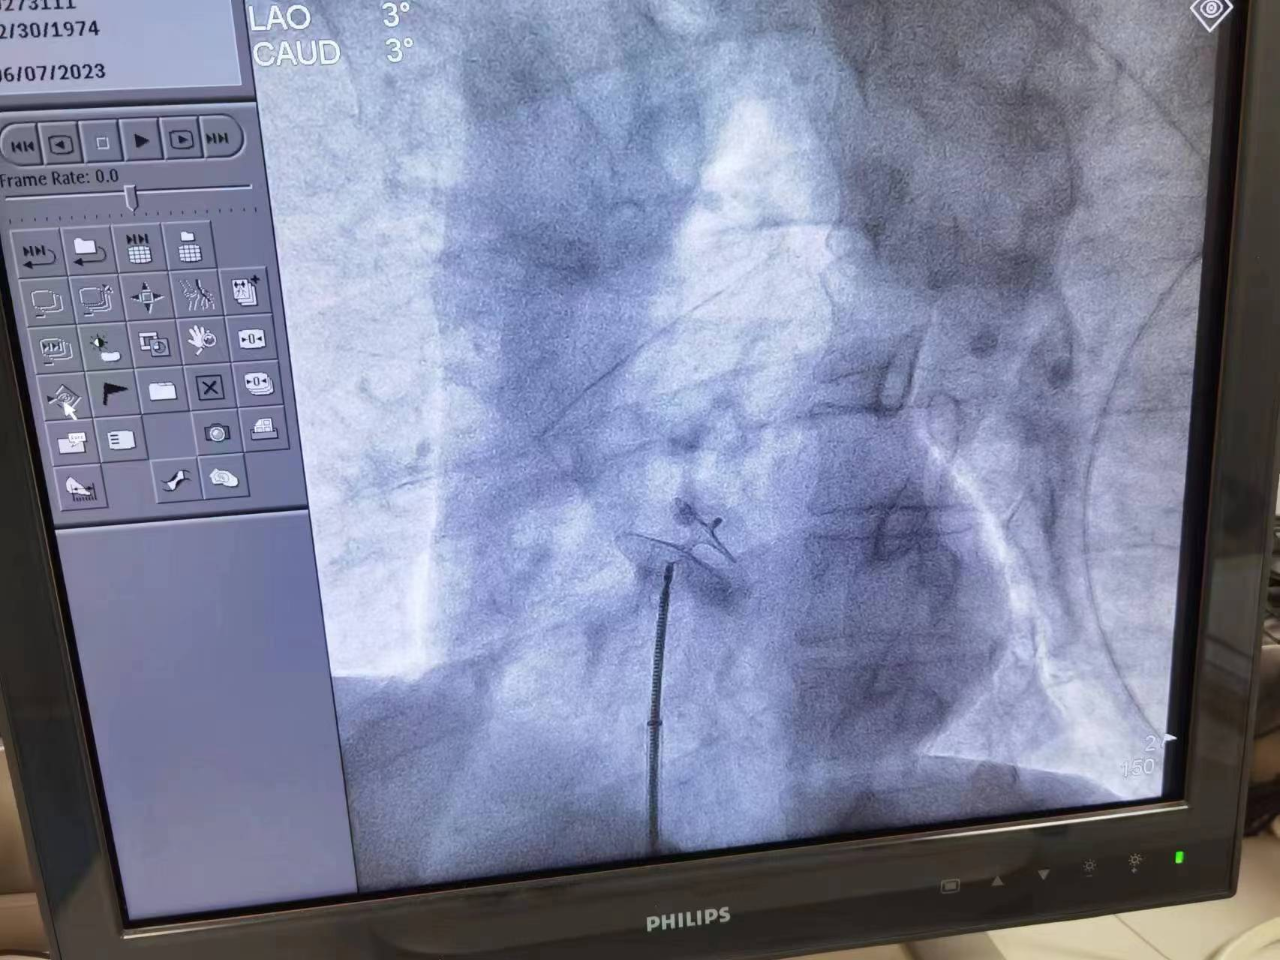

在武漢專家吳教授現(xiàn)場指導(dǎo)下,心血管內(nèi)科主任張靜、副主任醫(yī)師周建清及手術(shù)團隊成員一起為羅師傅實施了經(jīng)皮卵圓孔封堵術(shù)治療。

手術(shù)在導(dǎo)管室進行,上臺后周建清常規(guī)消毒鋪巾,熟練穿刺右側(cè)股靜脈。張靜主任沉著穩(wěn)定,準確將右心功能導(dǎo)管輔助送導(dǎo)絲穿過卵圓孔未閉(PFO)處,繼而卵圓孔封堵器至PFO處,分別釋放左右心房傘。

在X線及超聲下,確認封堵傘位置固定良好并做牽拉試驗,驗證封堵成功。手術(shù)整套流程如行云流水,全程不足30分鐘。羅師傅成為愛康醫(yī)院心血管內(nèi)科實施介入治療卵圓孔未閉患者的第一人。